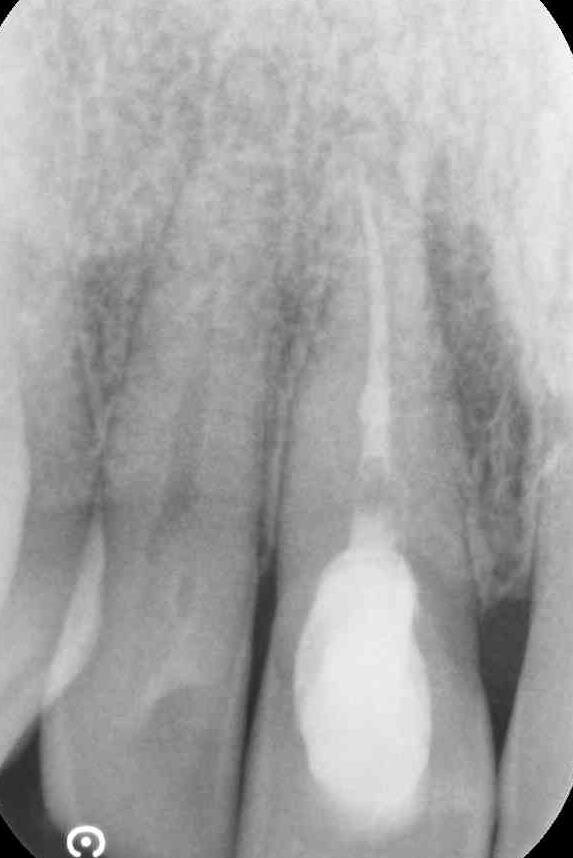

Nei primi mesi del 2016, tuttavia, il paziente perde l’impianto in sede 22, ha fastidio nel settore frontale e nota un “brufolino”, ma per il professionista è tutto a posto. Non convinto, l’insegnante effettua una consulenza da un altro odontoiatra e scopre che il dente 11 ha dei problemi. È compromesso da un processo infettivo cronico (area di rarefazione radiograficamente evidenziabile) con evidenza radiografica e una fistola, prima inesistente. C’è una perforazione iatrogena della radice del dente, con sbuffo di materiale radiopaco nel parodonto.

In parole semplici il paziente scopre che la terapia è stata mal eseguita e ha prodotto un danno (falsa strada). Risulta necessario un secondo intervento ortogrado e retrogrado da parte di uno specialista in endodonzia dal costo di 850 euro. Ai controlli successivi le problematiche rientrano. Il giovane insegnante protesta con il primo odontoiatra, chiede indietro quanto ha speso per il trattamento del dente 11 (ossia 250 euro) e per l’intervento endodontico di recupero del dente, 850 euro, per un totale di 1.100 euro.